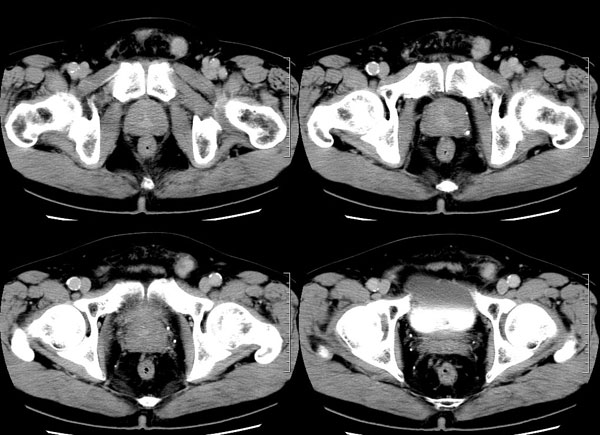

| 男性,69岁。自2个月前开始无意中发现左侧阴囊内一鸡蛋大小肿物,当时无伴疼痛等不适,未予重视。肿物逐渐增大,近段时间常伴左会阴部、腹股沟区牵扯不适,并于2周前在我院门诊行彩超检查提示“左侧附睾肿瘤可能,左侧睾丸鞘膜积液”。 专科检查:左侧阴囊肿大,其内可触及一鹅蛋大小肿物,表面光滑。肿物前部呈囊性感,后部质硬,按压无疼痛,无缩小,活动度良好。左侧睾丸未触及,透光试验(±)。                 王仕学发言:左侧睾丸见一密度不均肿块,边缘清楚,周围见水样密度影;考虑睾丸生殖细胞性肿瘤可能性大. 睾丸肿瘤占生殖系统肿瘤的3%-5%,占男性恶性肿瘤的0.5%-1.0%,其中生殖细胞性肿瘤占95%.睾丸肿瘤包括生殖细胞和非生殖细胞肿瘤两大类,前者占95%以上,后者不到5%.非生殖细胞肿瘤虽少见,但种类繁杂,主要有支持细胞、间质细胞和支持细胞-间质细胞瘤等功能性肿瘤,和间皮瘤、腺癌、横纹肌肉瘤、粘液性囊腺瘤、纤维上皮瘤、黑素神经外胚瘤、淋巴瘤等附属组织肿瘤。不同的病理类型的睾丸肿瘤发病率高峰不同,睾丸癌多发于35岁以前,精原细胞瘤发病高峰为30-35岁。精原细胞瘤约占睾丸肿瘤的60%,发病高峰在30-35岁。85%的患者睾丸有明显肿大,肿瘤局部侵犯力较低,肿瘤一般有明显界限。 手术:行“左侧附睾、睾丸、精索切除术”。 病理诊断:(左睾丸、附睾)肿物,为低分化腺癌。另送检(左精索远端)肿物,镜下亦为低分化腺癌。 免疫组化:ck(l)(++++)、cea(+++)、ca19-9(-)、psa(-)、plap(-)、p53(-)、vimentin(-)。 原贴地址:http://www.radinet.com.cn/forum_view.asp?forum_id=4&view_id=30707 |